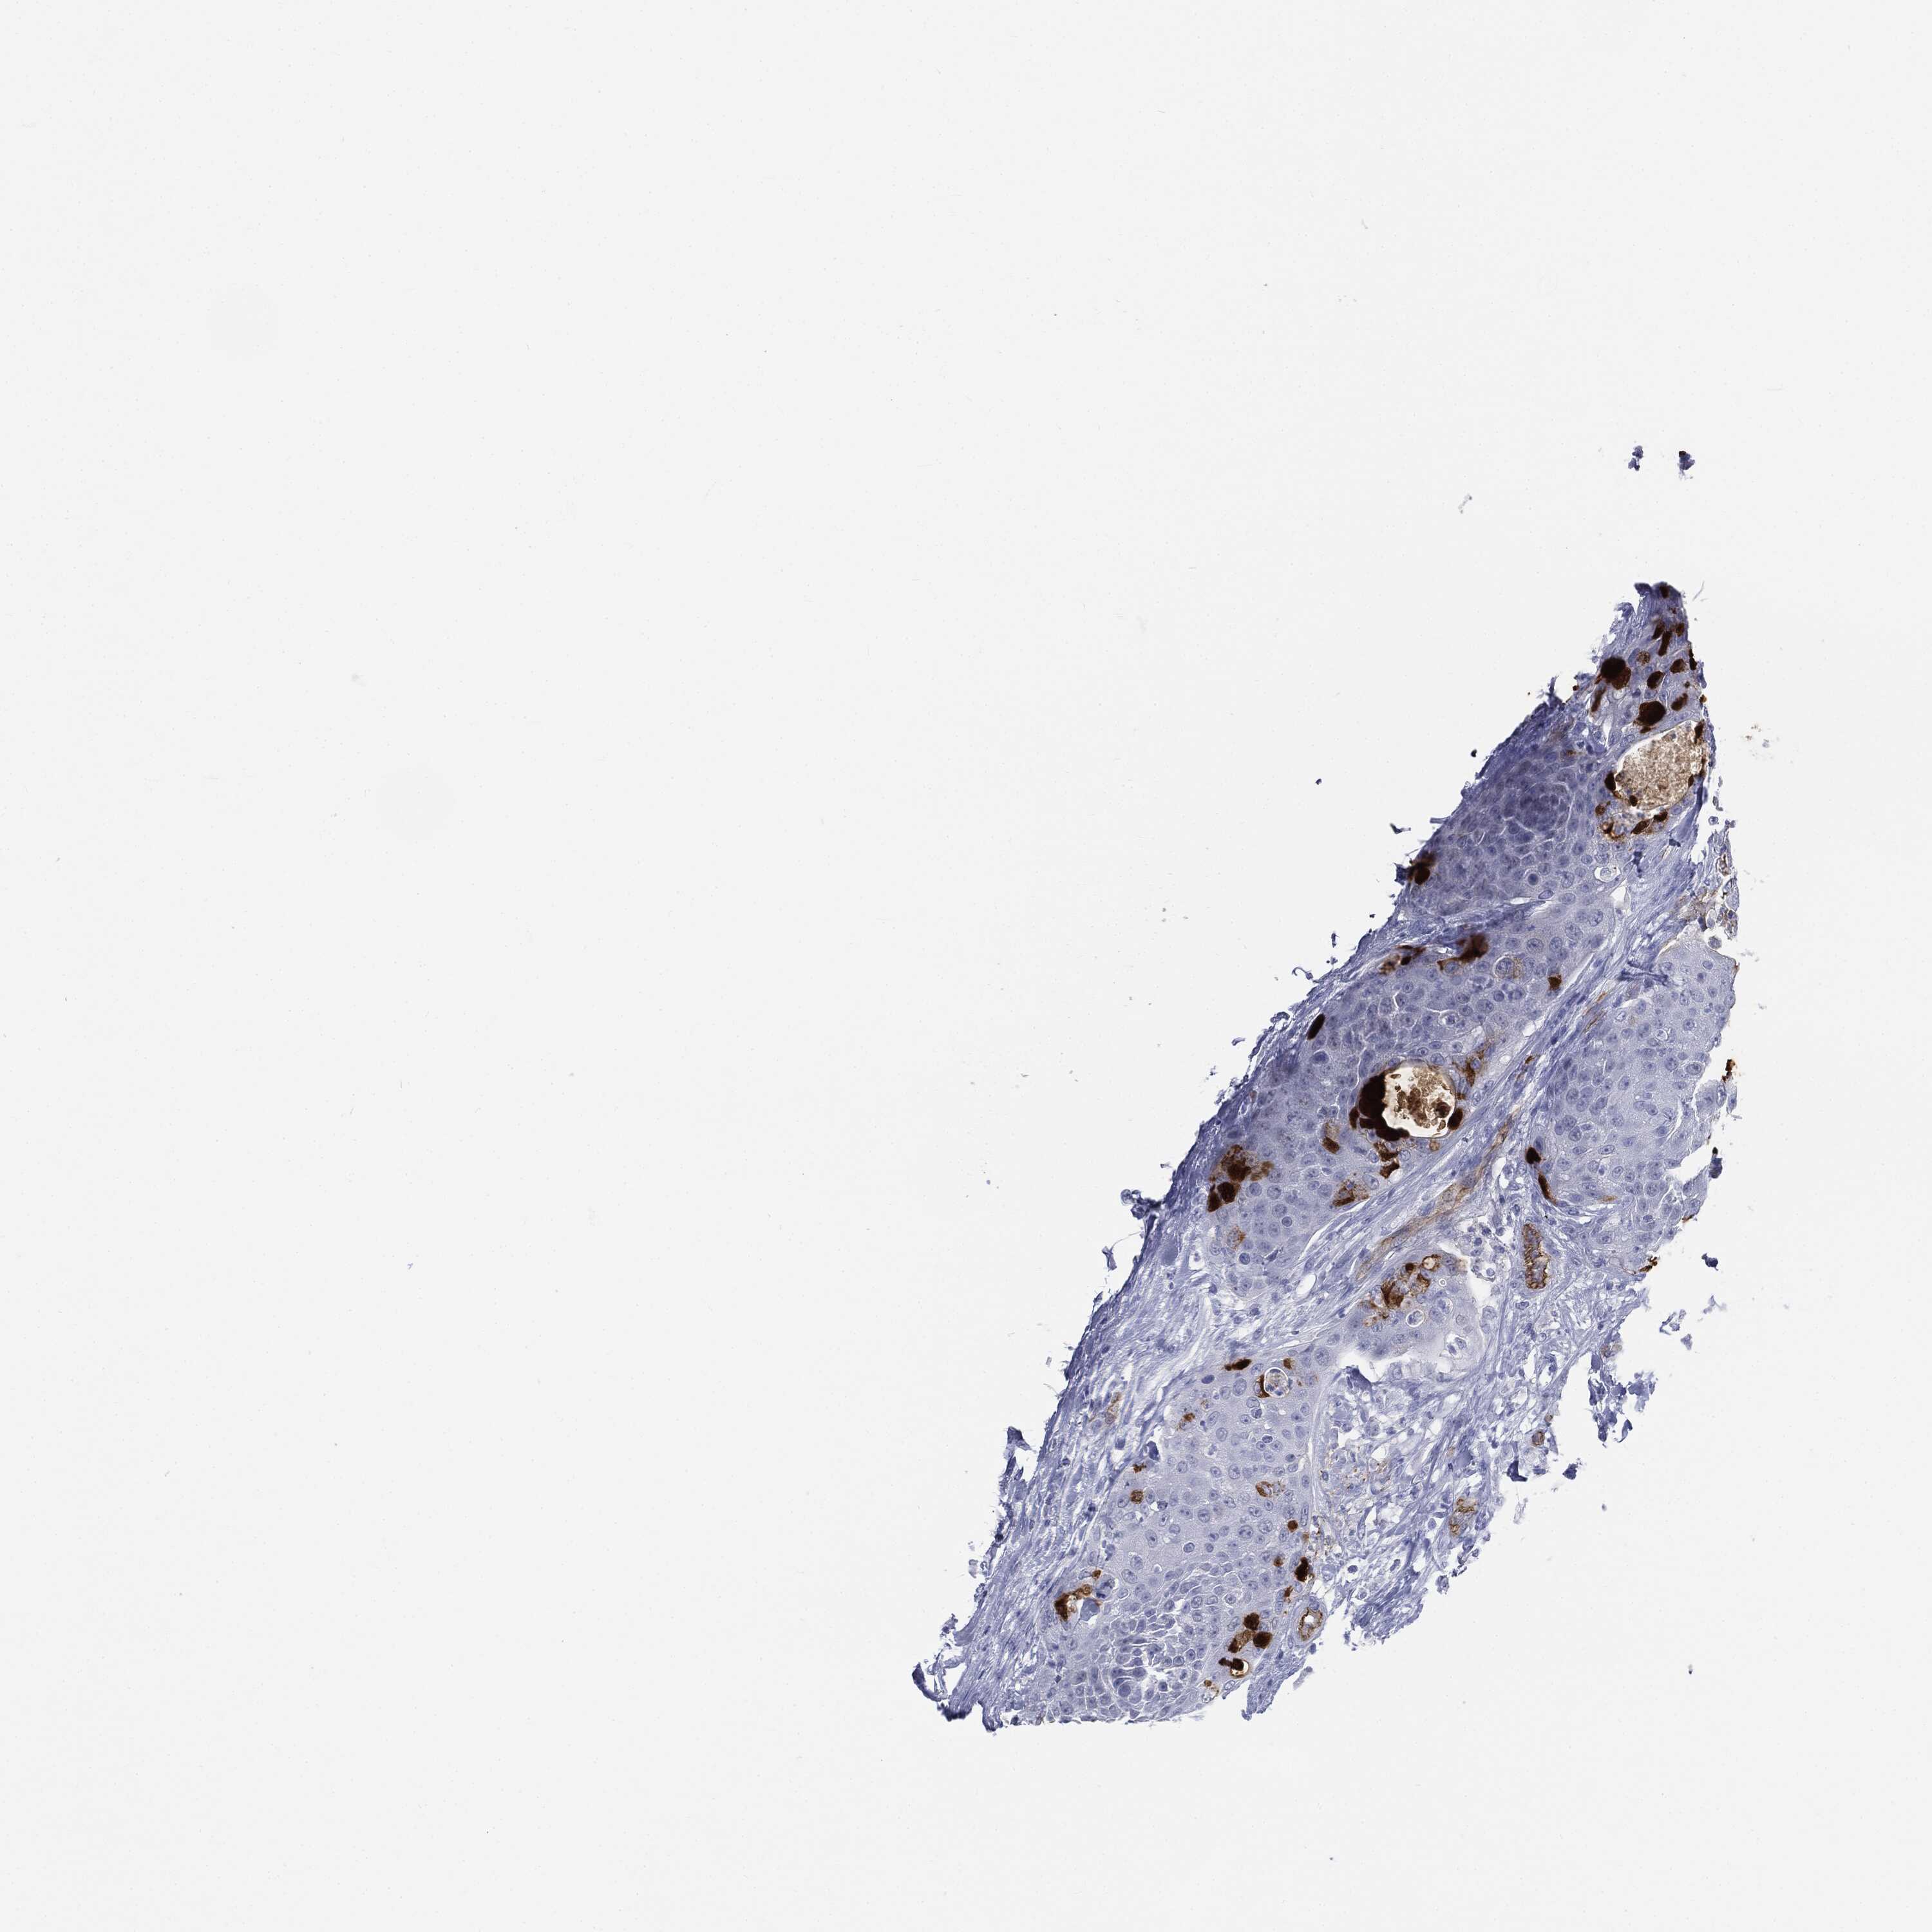

UROTHELIAL CANCER - Protein expressioni

A mouse-over function shows sample information and annotation data. Click on an image to view it in a full screen mode. Samples can be filtered based on level of antibody staining by selecting one or several of the following categories: high, medium, low and not detected. The assay and annotation is described here.

Note that samples used for immunohistochemistry by the Human Protein Atlas do not correspond to samples in the TCGA dataset.

Antibody stainingi

Antibody staining in the annotated cell types in the current human tissue is reported as not detected, low, medium, or high, based on conventional immunohistochemistry profiling in selected tissues. This score is based on the combination of the staining intensity and fraction of stained cells.

Each image is clickable and will lead to virtual microscopy that enables deeper exploration of all samples and also displays staining intensity scores, fraction scores and subcellular localization as well as patient and tissue information for each sample.

Urothelial carcinoma, High grade

Urothelial carcinoma, NOS

Urothelial carcinoma, Low grade

Adenocarcinoma, NOS